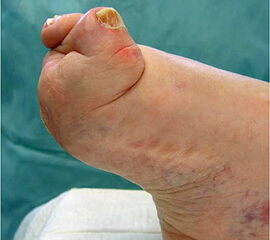

Medialer Hohlfuß (Ballenhohlfuß, Pes cavovarus)

• Druckdolenz unter dem ersten Metatarsalekopf

• Druckdolenz unter dem lateralen Rückfuß

• Laterale Instabilität im oberen und unteren Sprunggelenk, rezidivierende Inversionstraumata

Der „klassische“ mediale Hohlfuß (Ballenhohlfuß) führt durch die, gegenüber den übrigen Metatarsalia, plantarisierte Stellung des Metatarsale I auf ebenem Untergrund zu einer pronierten Vorfußstellung, welche den Rückfuß unter Belastung über die Drehachse des Chopart- und Subtalargelenkes sekundär in eine Calcaneus varus Deformität zwingt. Die schmerzhafte Beschwielung unter dem Metatarsale I Kopf stellt häufig das erste Symptom dar. Bei neuromuskulärer Genese fällt eine schnellere Ermüdung der Fußmotorik bei gewohnter Gehstrecke auf. Biomechanisch stehen die Übermacht des M. peroneus longus bzw. die Schwächung des M. tibialis anterior im Vordergrund (Abb.17) 13.

Infolge der konsekutiven Varisierung des Calcaneus neigt der Patient zu Inversionstraumata des oberen und unteren Sprunggelenkes. Unsicherheit besteht auf unebenem Untergrund. Eine Überdehnung des lateralen Kapselbandapparates des oberen Sprunggelenkes mit Schmerzen in der lateralen Rückfußregion und eine vermehrte Beschwielung der plantaren lateralen Calcaneusregion prägen das klinische Bild. Infolge der mangelnden Fußhebung kann gelegentlich zusätzlich ein Spitzfuß entstehen, da die Funktion des plantarflektierenden M. triceps surae überwiegt (Abb. 18). Langfristig begünstigt die auch im oberen Sprunggelenk erhöhte Belastung der medialen Gelenkanteile die Entstehung einer medial betonten Arthrose 14.